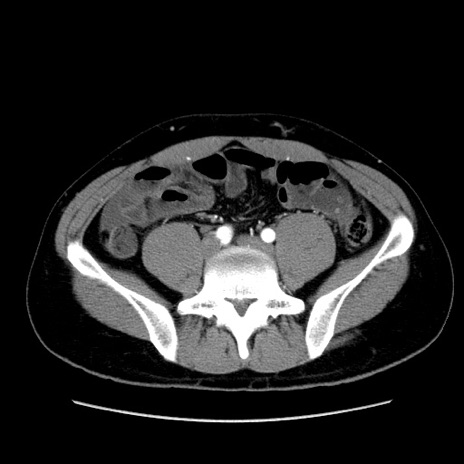

症例36(横断像)

【症例】20歳代 男性

【主訴】心窩部痛

【現病歴】今朝より上腹部痛あり。一旦軽快していたが再度出現したため救急要請。昨日夕に白身の魚を含む刺身を食べた。

【身体所見】BP 136/89mmHg、HR 74/min、BT 37.0℃、腹部:膨満、軟、心窩部に圧痛あり。反跳痛なし、筋性防御なし、腸雑音やや亢進あり。

【データ】WBC 17700、CRP 0.48